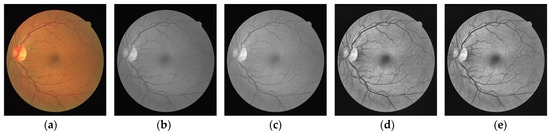

4.1. Datasets

4.2. Fundus Image Preprocessing and Patch Extraction